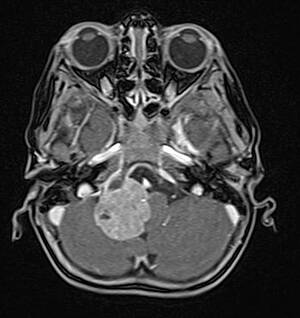

Rhabdoide Tumoren können in allen Geweben des Körpers entstehen. Am häufigsten betreffen Sie das Gehirn und das Rückenmark, die Nieren und die Leber, Hals-, Oberschenkel-, Brustwand- und anderer Weichgewebe (siehe Abb. 1a-c). Rhabdoide Tumoren des Gehirns werden auch als AT/RT („atypischer teratoider, rhabdoider Tumor“), solche der Nieren als RTK („rhabdoid tumor of the kidney“) und solche der Weichgewebe als MRT („malignant rhabdoid tumor“) bezeichnet.

Abb.1a: Rhabdoider Tumor des Gehirns